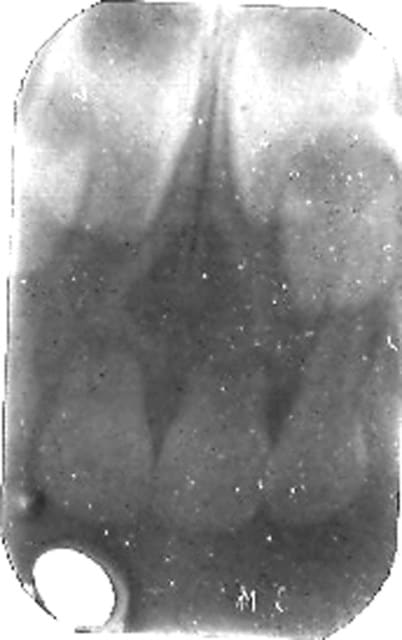

voici une photo (désolé pour la qualité j'ai un scanner trés moyen) je travaille encore à l'ancienne pour les radios !!

Kgjuillet07 j3r0oc - Eugenol

ton kyste ne semble pas correspondre à une pathologie des lacteales

qu'en est il de l'occlusion:supraclusion?

j’ai essayé d’améliorer ton cliché

Kyste 1 copie xdiu7l - Eugenol

bien sur ce n'est pas le seul élément diagnostic???

cyril,

ce qu'on essaye ts de te dire c'est que tu ne peux etablir de diagnostic et de plan de traitement sans panoramique au minimum (si tu n'en a pas demandes en une,si tu en as une,mets la pr qu'on puisse te donner un avis),et ns t'aider malgré le louable essai d'amelioration de ta retro par bjc(merci),

Il s'agit certainement d'un antécédent de traumatisme avec resorption radiculaire de 51+61.

Quant aux 2 petites dents ce sont les latérales définitives.Donc il n' y a pas de surnuméraires.

si non, surveillance et c'est tout, jazz a raison, sur cette radio où voyez vous des surnuméraires?

POur moi la racine de 62 est intacte.Ce sont les 51 et 61 qui sont résorbées.

Au dessous des germes de 11 et 21 ce sont peut-être des germes de dents surnuméraires (en rouge), ils semblent symétriques; il faudrait voir sur la pano où sont 12 et 22: Mais je ne vois ni 62 bis ni 22 bis.

Alors, je me dis que peut-être le kyste résorbe les racines de 51 et 61, qu'il gène l'évolution de 11 et 21.

Sur cette radio, on ne voit rien d'autre.